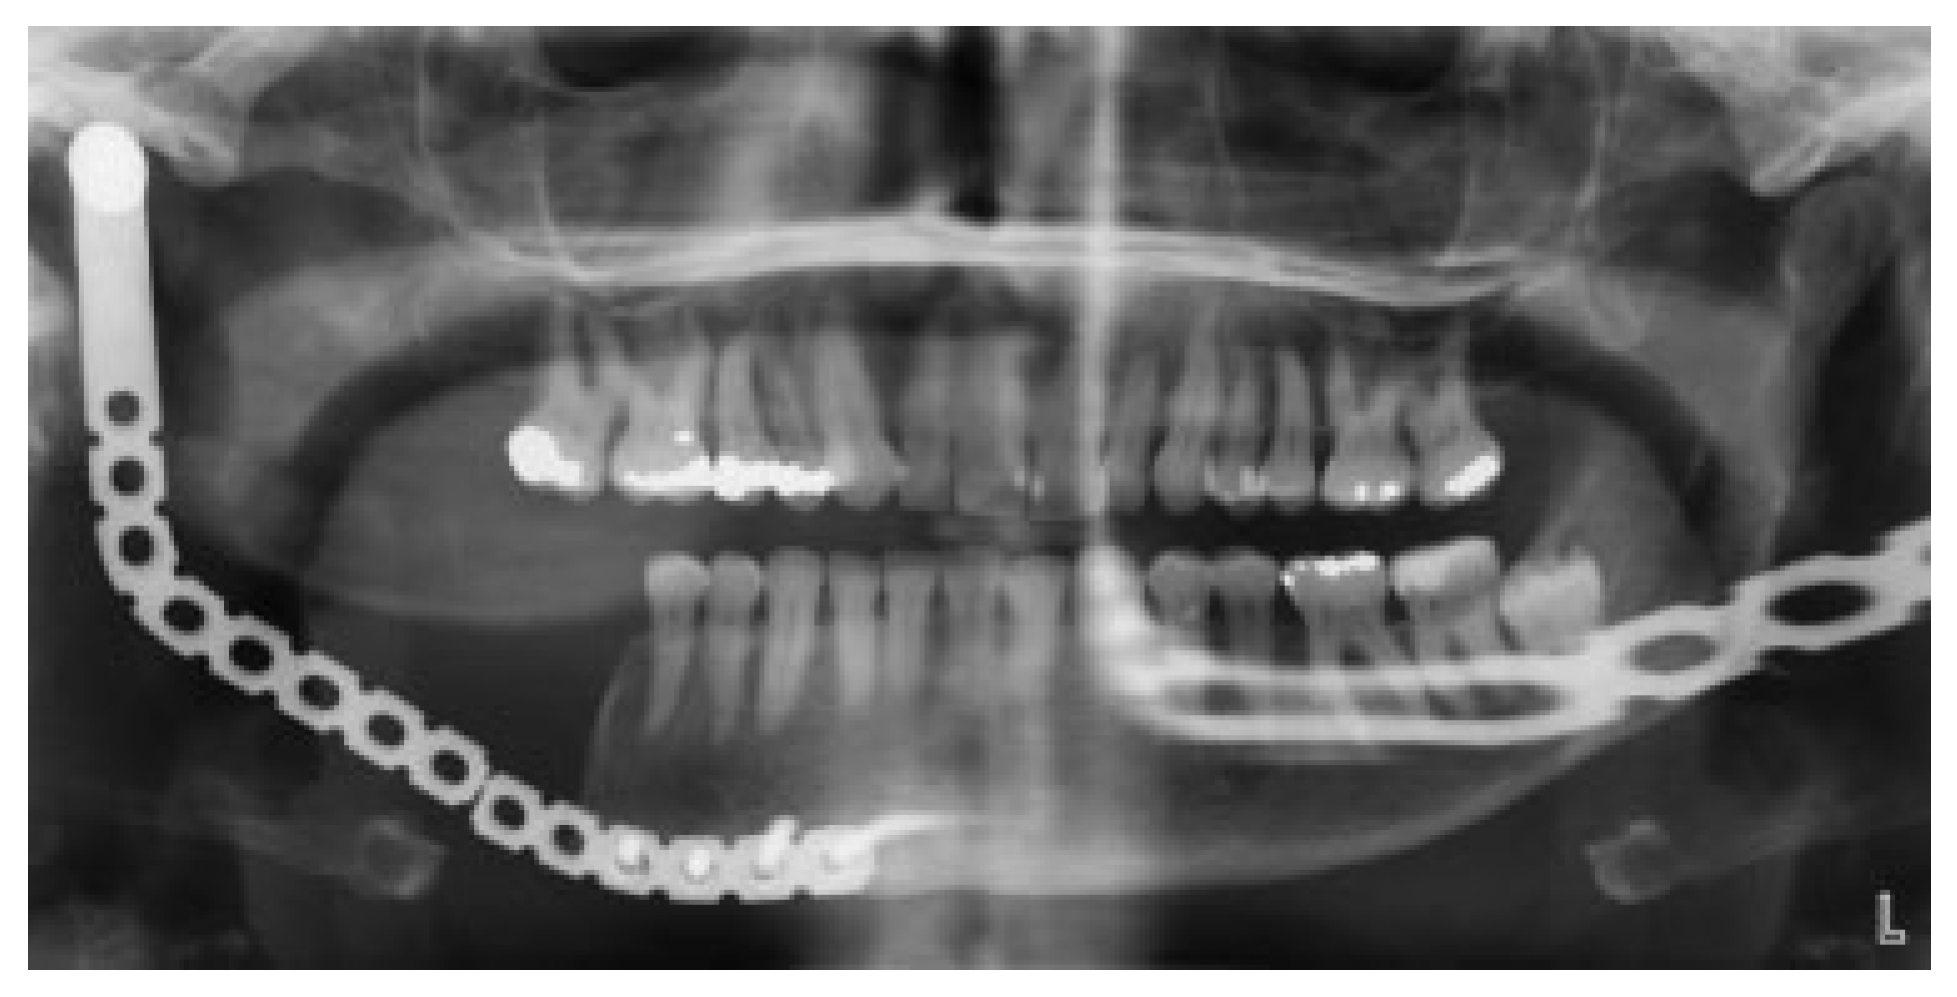

In March 2015, the patient returned to the clinic almost 15 years after surgery, complaining of “weird bite” and pain upon chewing. At this time, she was seen by the author. She described a cracking sound from the jaw couple of days earlier while chewing. Her medical history was once again noncontributory. Clinical examination revealed a deviated chin to the right and slight asymmetry in the right cheek (Figure 2). Furthermore, there was obvious malocclusion and the range of motion was restricted (Figure 3). The intraoral lining was intact. An orthopantomogram disclosed a fracture of the reconstruction plate in the body area. The condylar head was intact (Figure 4).

Figure 4. Orthopantomogram reveals fracture of the reconstruction plate.